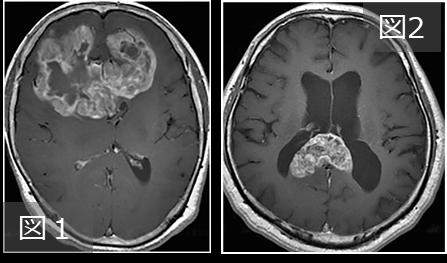

図1はbutterfly glioblastomaの典型像で、両側前頭葉に腫瘍進展しています。脳腫瘍分類に記載の通り、片側大脳半球に起源を有し脳梁を介して対側進展している、ことに矛盾しません。一方で、図2は大脳半球に腫瘍成分がなく、脳梁に限局しています。即ち、図2の症例は脳腫瘍分類の記載に合致しないことになります。そこで、butterfly glioblastomaは一様な腫瘍ではないのでは、という疑問が生じました。